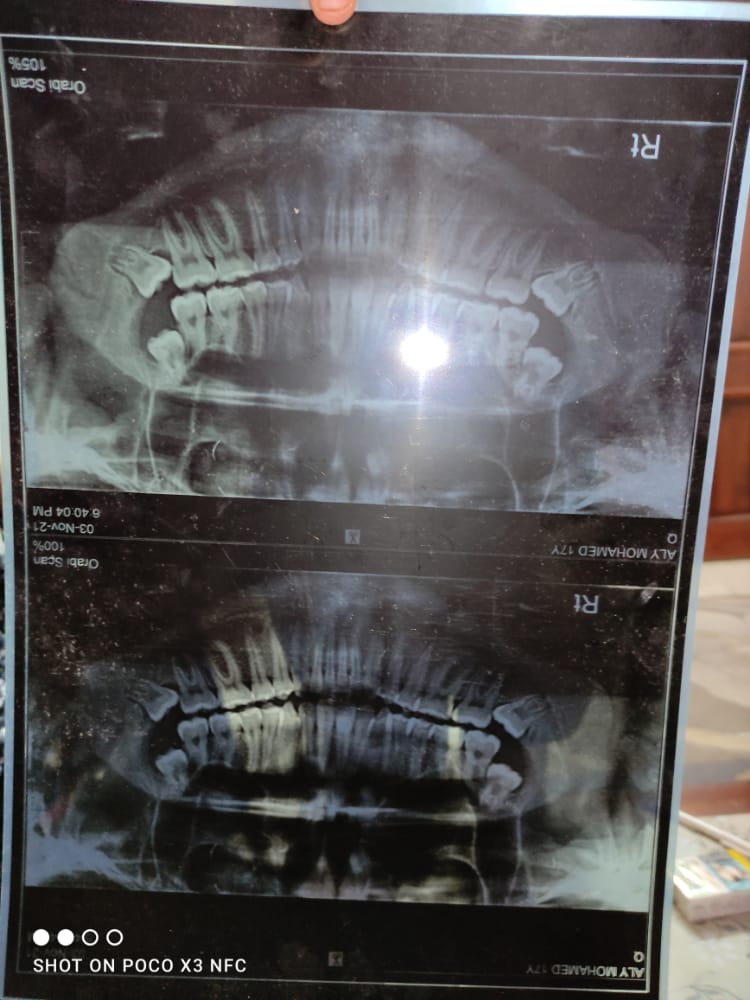

تلقى اللواء محسن شعبان مدير أمن القليوبية إخطارًا من مأمور قسم أول شبرا الخيمة، بتلقيه إخطارًا من مستشفى ناصر العام؛ باستقباله الطالب محمد علي مبروك، بالصف الثالث الثانوي بالمدرسة الثانوية الصناعية بنين بشبرا الخيمة، قسم سيارات، بإصابته بكسر بالفك إثر قيام زميله في الفصل بالتعدي عليه، وضربه بـ البوكس في وجهه.

وكشفت التحريات أن الواقعة تمت داخل أروقة المدرسة بسبب تشاجر الطالبين معًا، لقيام المجني عليه بمعاتبته للمتهم بتناوله سجائر، فتعدى الأخير عليه بالضرب، وجرى تحرير محضر رقم 30396 وتولت النيابة التحقيق.